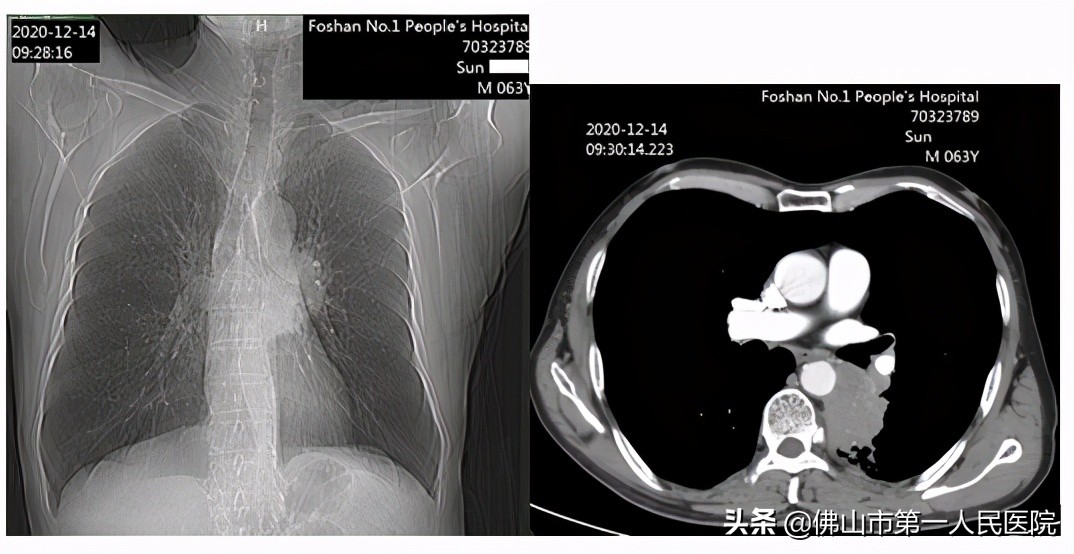

孙大爷于当年12月慕名来到了佛山市第一人民医院肿瘤靶向介入科治疗。该科史德刚主任分析了患者的病情和影像资料以后,为他复查了胸部CT增强扫描及重建,诊断为肺癌并阻塞性肺炎,左肺门、纵隔淋巴结待排转移,双肺肺气肿,主动脉及冠状动脉硬化。拟行左下肺癌射频消融治疗,靶向免疫和综合治疗。

史主任给患者做了左肺癌射频消融术,考虑到肺癌病灶位于胸主动脉和左下肺动脉之间,分叶状,不易完全消融,给患者服用抗肿瘤血管生成治疗,并进行免疫治疗和左侧支气管动脉灌注化疗+栓塞治疗。

治疗1个月后,患者复查胸部CT增强扫描及重建,对比就诊前片,左下肺背段病灶呈空洞样改变,实性成分明显减少;左下肺出现炎症病灶,部分支气管扩张,建议抗炎治疗后复查。双肺气肿等大致如前。

史主任表示,本例患者诊断肺鳞癌,根据患者的一般情况以及肿瘤位置分析,不宜行手术切除治疗,因为肿瘤位于胸主动脉和左下肺动脉之间,病变形态不规则,向前生长进入纵膈,手术不易切除干净。本例患者双侧肺气肿,糖尿病,10年前曾经有冠心病溶栓治疗的病史,都增加了治疗的风险。经过肿瘤靶向介入科综合治疗方案的实施以后,达到了CR根治标准,近期效果非常显著。出院时,当医生拿着治疗后照的CT片告诉孙大爷,他的肺癌病灶“呈空洞样改变,实性成分明显减少”时,孙大爷高兴地说:“看来我的肿瘤真是不翼而飞了!”